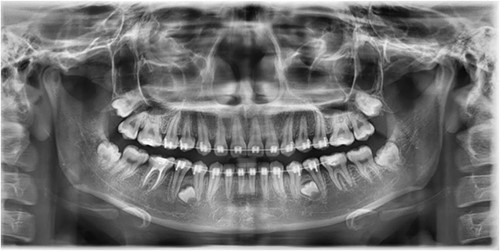

A Neumann full-thickness buccal flap was utilized to remove these during the course of orthodontic treatment. The shortcoming of the buccal surgical removal approach is that although it is better for visualization, it poses a high risk of trauma to the adjacent teeth or nerves [4, 5]. As the premolar was being removed on the right side, there was a fracture of the root apex (Fig. 2). On the left side, the premolar bud could be removed without any trauma to the adjacent tooth roots. After months of follow-up, there was normal bone formation, and no other symptoms were identified (Fig. 3).

Follow-up panoramic image 1-year after removal of the supernumerary premolars.